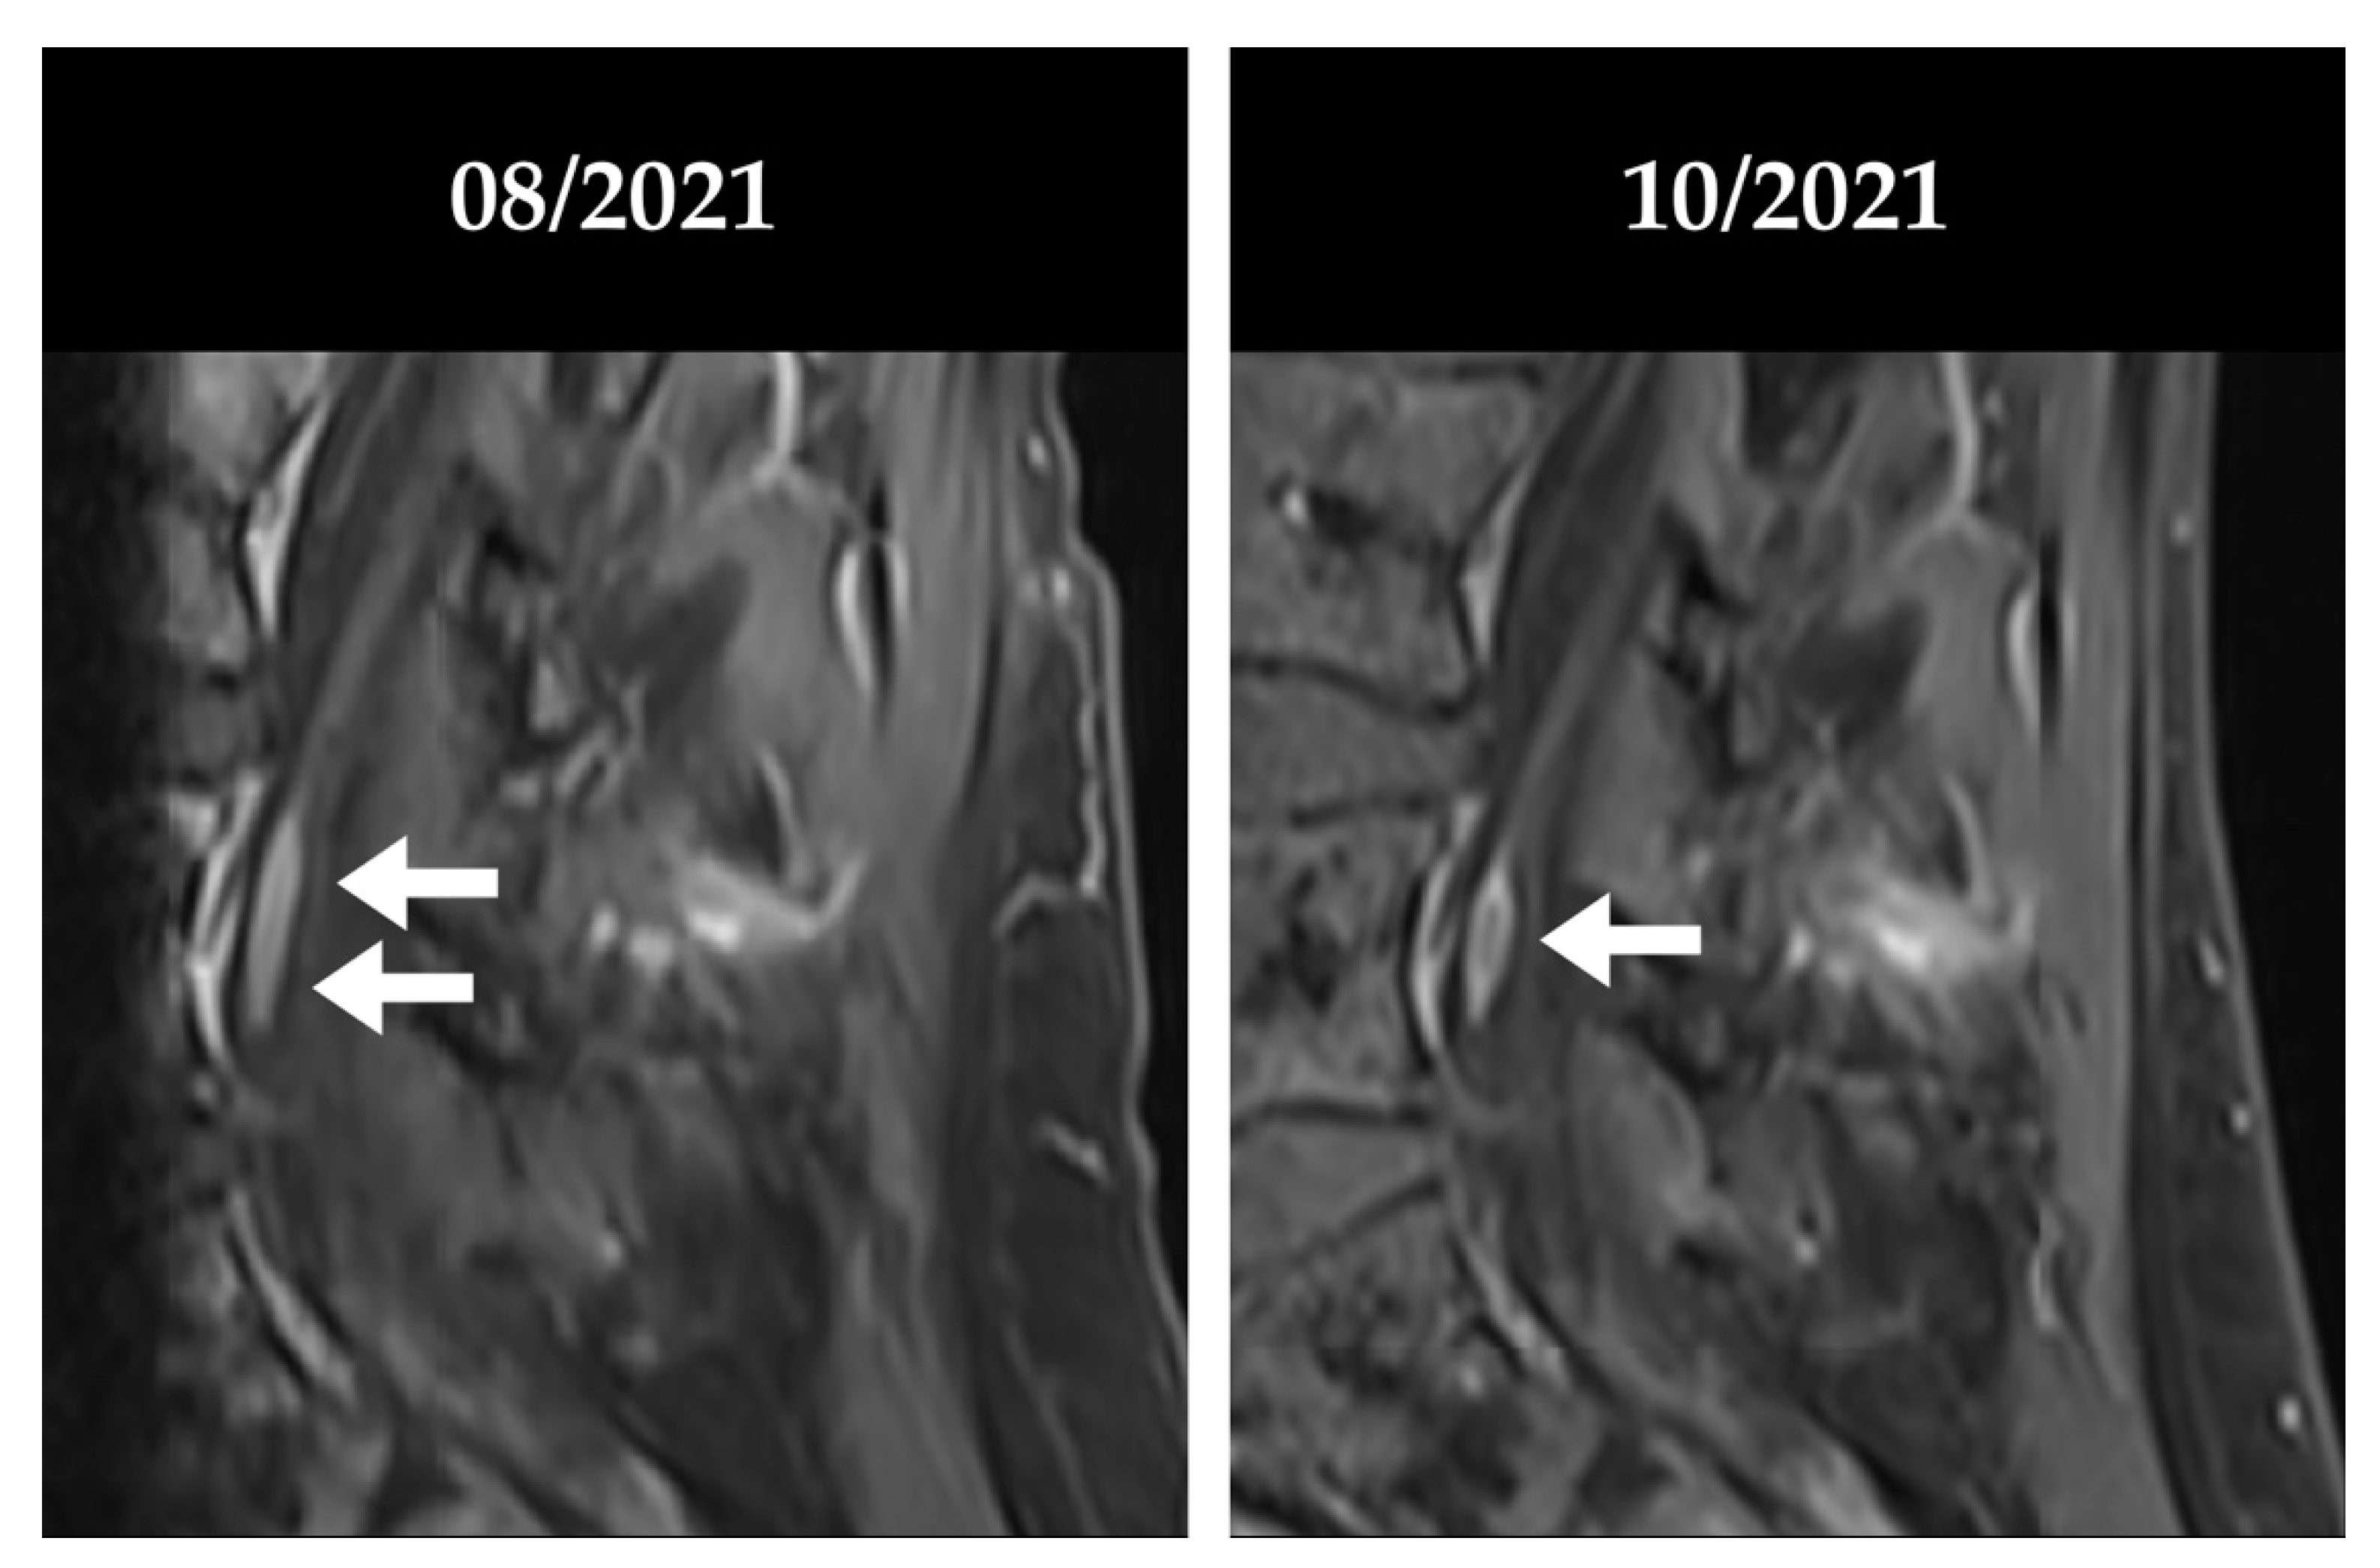

4.1. Patient #1

4.2. Patient #2